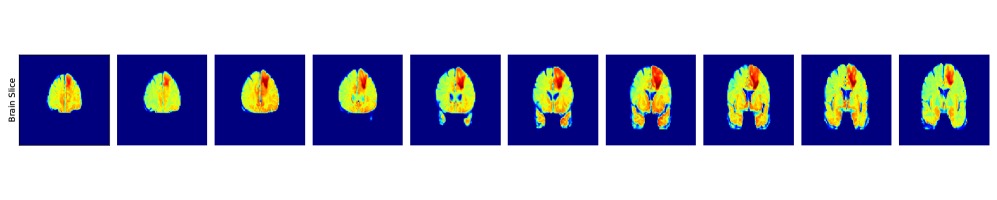

Our objective is to perform brain tumor segmentation on the BraTS2020 dataset [30]. This dataset contains 3D brain MRI volumes. The data is divided into two categories: (1) High-grade gliomas (HGG), (2) Low-grade gliomas (LGG). Each brain scan is accompanied by a simplified segmentation mask defined as 0: non-tumor tissue pixels and 1: tumor tissue pixels. We train our segmentation model using brain scans with HGG tumors, from which we select 190 for training, 10 for validation, and 10 for testing. During training, we apply a range of augmentation techniques. We refer to SI B.6 for further details on the datasets and employed augmentation techniques; we also include an ablation on the noise corruption technique.

Our evaluation is conducted on 10 held-out HGG brains and an additional set of 10 LGG brains. For the HGG cases, we evaluate the model not only on FLAIR MRI scans, which were used during training, but also on T2T_{2}-weighted scans, representing a different MRI modality. For the LGG cases, performance is assessed on both axial (z-axis) slices, aligned with the training direction, and x-axis slices, offering a side view of the brain and allowing us to test the model’s generalization to previously unseen anatomical orientations.

SI B.6, Fig. 34 shows the relation between relative L1L_{1} segmentation error and our likelihood certificate across four test scenarios. Most low-error cases are correctly classified as ID, while nearly all high-error cases (relative L11.0L_{1}\geq 1.0) are identified as OOD. Furthermore, it is crucial to highlight that our approach effectively identifies OOD samples originating from a different MRI modality, namely T2T_{2} MRI scans (see subfigure 3 in Figure 34).

Aggregating all datasets, the 2d histogram of error vs. likelihood (SI B.6, Fig. 35(left)) shows high density around low likelihood and errors near 1.01.0, i.e., OOD. Low-error points cluster near the threshold but remain ID. The log-likelihood histogram (middle) is right-skewed, favoring higher values. Finally, error histograms (right) confirm that ID samples are mostly low-error, while OOD samples are dominated by high-error cases, with some low-error outliers.